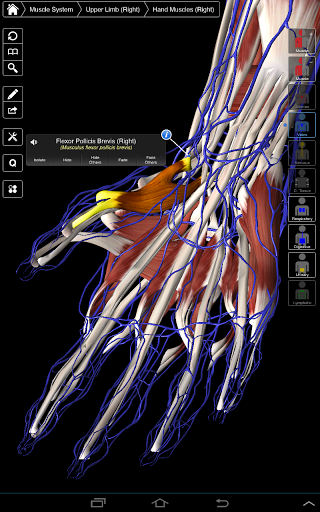

Essential Anatomy 3 représente la toute dernière technologie 3D révolutionnaire et un design innovant. Un moteur graphique 3D de pointe, construit sur mesure par 3D4Medical à partir de zéro, alimente un modèle anatomique très détaillé et fournit des graphiques de qualité exceptionnelle qu'aucun autre concurrent ne peut atteindre.

L'application représente une approche unique à l'apprentissage de l'anatomie générale. Les graphismes sont inégalés et rendent l'apprentissage, grâce à l'utilisation de contenu informatif et de fonctionnalités innovantes, une expérience riche et engageante.

Essential Anatomy 3 est réactif, visuellement magnifique et sans effort. L'application est entièrement 3D, ce qui signifie que vous pouvez voir n'importe quelle structure anatomique dans l'isolement, ainsi que de n'importe quel angle.

---- Plus de 4000 structures anatomiques très détaillées

---- Nomenclature latine pour chaque structure anatomique